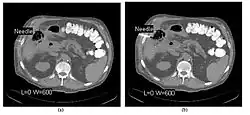

- CT Fluoroscopy (CTF) has also been referred to as Continuous CT or Real-Time CT since it involves generating tomographic images at sufficiently high frame rates to allow guidance of needle placement in small or deep-seated lesions. Applications can include biopsy of thoracic lesions, biopsy/drainage of pelvic lesions, vertebroplasty and drainage/aspiration of intracranial haematomas. The advantages of CTF include increased target accuracy and reduced procedure times[45].

- The major difference to a conventional CT system is that high speed reconstruction techniques are applied, and that an operator panel, exposure footswitch and image monitor are installed in the scanning room for use by the interventionist. Controls are generally available for table movement, gantry tilt, laser grid definition and fluoroscopic factors. The other significant operational change relates to the choice of tube current which is typically 30-50 mA in CTF. This should be compared with typical screening currents used in conventional fluoroscopy of up to 5 mA, so that CTF can be regarded as a high dose procedure. In this context, additional beam filtration can be introduced automatically for CTF procedures to reduce patient exposure by up to 50%, for example. Furthermore, the use of protective gloves and needle holders can reduce the radiation exposure to the hands of the interventionist.

- The value of N is typically 30o, 45o or 60o, with frame rates of 12, 8 and 6 frames per second, respectively. In the case of 60o updates and 6 frames per second, the delay between each image is 0.17 seconds. A Last-Image-Hold (LIH) technique can be used while the image is being updated with the resulting time lag being considered by the interventionist in terms of biopsy technique. Example images are shown in Figure 7.15.11. The display of three adjacent slices of thickness 5 mm with MDCT scanning can be used to improve visual feedback to the interventionist as the needle progresses. In addition, multi-planar reconstructions (MPR) and volume rendered 3D images can be used to enhance fine control.